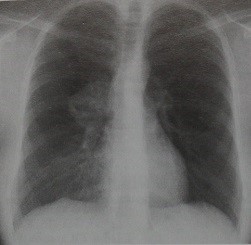

Болезнь Кастлемана у женщины 30 лет. На обзорной рентгенограмме грудной клетки видна опухоль с четко очерченными полициклическими контурами, локализующаяся в воротах правого легкого, которая не беспокоила больную и была выявлена случайно. Рентгенологически опухоль невозможно отличить от лимфомы и опухолей другой этиологии.При гиалиново-сосудистом типе болезни Кастлемана выраженное контрастное усиление пораженных лимфатических узлов на КТ может помочь установлению типа лимфомы.